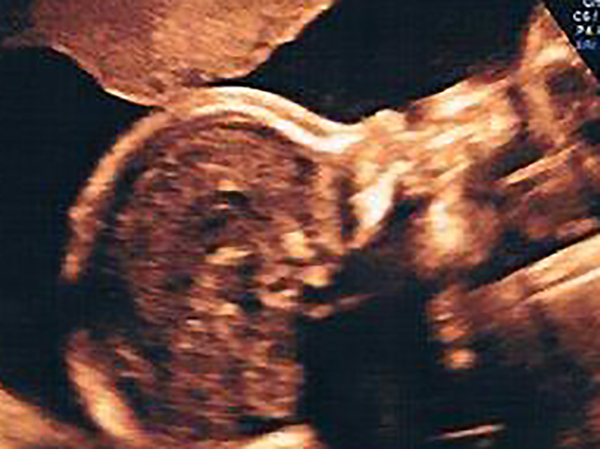

Der Chefarzt beginnt am Köpfchen und untersucht den Embryo Schritt für Schritt mit einer Menge Genauigkeit und Sorgfalt.

Und immer wieder höre ich Sätze, die runter gehen wie Öl. Dass alles sehr gut aussieht, im Normalbereich und bestens entwickelt ist. Klasse! Das freut mich total.

Außerdem hätte ich ein sehr quirliges Mädchen, das sich sehr gekonnt bewegt – in dieser Form könnten das sowieso nur Kids, die total gesund sind.

Zu Hause zeige ich meinem Schatz ganz begeistert die Ultraschallbilder. „Hey, die Kleine sieht ja aus wie du“, findet er beim „Foto“ des Gesichtes. Und was sei das Füßchen süß!